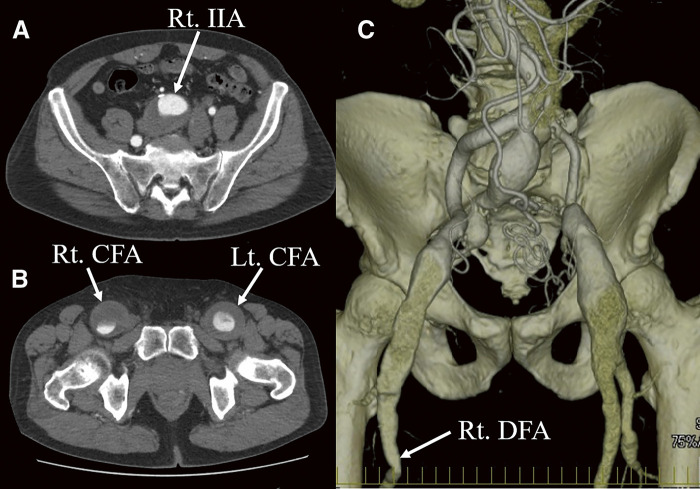

我们报告了一例股总动脉瘤病例,这是免疫球蛋白 G4 相关疾病(IgG4-RD)的一种极为罕见的表现形式。一名 79 岁的男性患者在 60 岁时因腹主动脉瘤破裂而接受了急诊腹主动脉瘤修补术,之后右侧髂内动脉、右侧股总动脉和左侧股总动脉都出现了增大的动脉瘤。因此,用延伸到右侧股深动脉的移植物替代了右侧髂动脉,同时重建了右侧髂内动脉。对切除的股总动脉壁进行的组织病理学检查证实了 IgG4-RD 的诊断。

We present a case of a common femoral artery aneurysm as an extremely rare manifestation of immunoglobulin G4-related disease (IgG4-RD). A 79-year-old male, who underwent emergency abdominal aortic aneurysm repair at age 60 due to rupture, developed enlarging aneurysms of the right internal iliac artery, the right common femoral artery, and the left common femoral artery. Consequently, the right iliac artery was replaced with a graft extending to the right deep femoral artery, also reconstructing the right internal iliac artery. Histopathological examination of the resected common femoral artery wall confirmed the diagnosis of IgG4-RD.